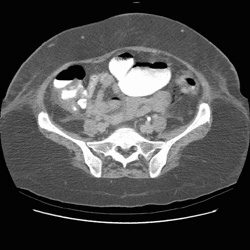

RADIOLOGY: GASTROINTESTINAL: GI: Case# 33130: ISCHEMIC COLON. The patient is a fifty-four year old female status post orthotopic liver transplant with episodes of hypertension, temperature spikes and seizures. 1) Portal venous gas with gas in the mesenteric veins and pneumatosis of the colon as described above. Most likely etiology would be ischemic episode involving the distribution of the IMA. 2) Splenomegaly, varices and moderate amount of free intraperitoneal fluid. 3) Small anterior right pneumothorax and bilateral pleural effusions.